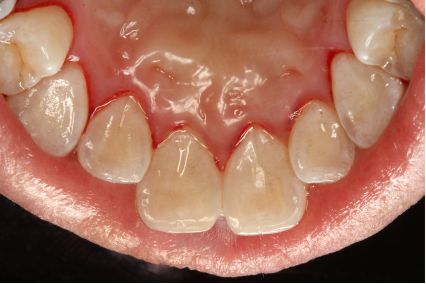

女,38岁,主诉牙龈出血1年,无系统疾病及药物过敏史。检查:牙列式18-27、37-47;18伸长,无咬合;口腔卫生欠佳,可见牙石、软垢,后牙区牙石软垢较多,全口牙龈边缘充血水肿,探诊出血阳性,牙周探诊深度3-4mm。诊断为慢性牙周炎(轻度)。

术前